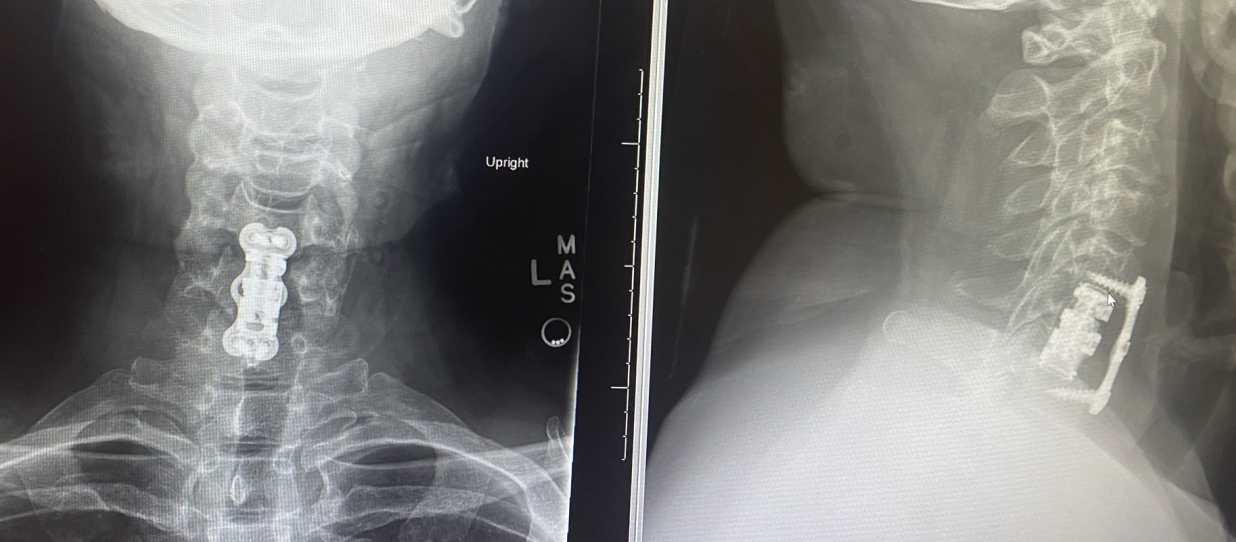

Since the 2025 holidays, my life has been upside down. On Dec 11th, I went to the ER with shooting pain in my arms and hands — and was turned away. Two weeks later, my doctor took one look and sent me straight back. The result:

Hardware in spine